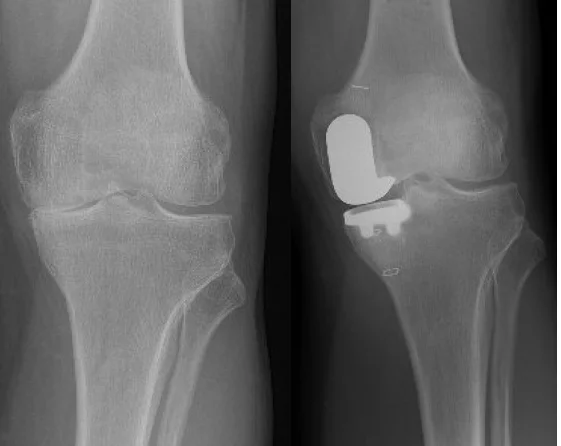

Η μονοδιαμερισματική αρθροπλαστική γόνατος αναφέρεται σε μια χειρουργική διαδικασία για ασθενείς με εντοπισμένη βλάβη σε ένα διαμέρισμα (τμήμα) της άρθρωσης του γόνατος.

Για παράδειγμα, μπορεί να αντικατασταθεί μόνο το έσω ή το έξω μέρος της άρθρωσης, για να αντιμετωπιστεί μια εστιασμένη πάθηση. Αυτή η χειρουργική επέμβαση αντικαθιστά, δηλαδή, ένα φθαρμένο τμήμα του γόνατος, αφήνοντας ανέπαφα τα υγιή τμήματα.

2. Κατά την επέμβαση, ο γιατρός αφαιρεί το φθαρμένο μέρος του γόνατος και προετοιμάζει το σημείο για την τοποθέτηση του εμφυτεύματος. Το εμφύτευμα – ή πρόθεση – που αποτελείται από μέταλλο και πλαστικό, τοποθετείται με ακρίβεια. Αντικαθίσταται έτσι, το κατεστραμμένο τμήμα. Οι υγιείς χόνδρινες επιφάνειες του υπόλοιπου γόνατος παραμένουν ως έχουν.